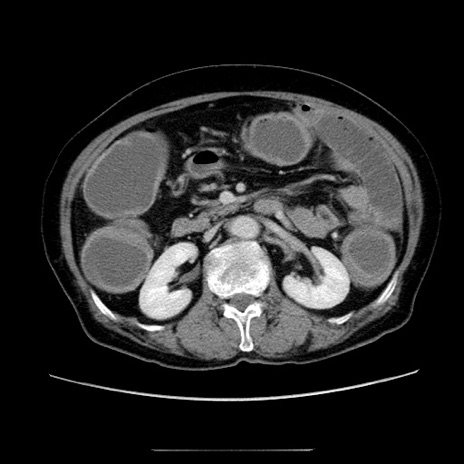

冠状断像

【症例】70歳代女性

【主訴】お腹が張る

【現病歴】1週間くらい前から腹部膨満の自覚あり。昨日夜から増悪したため、本日救急外来受診。

【身体所見】意識清明、BT 36.5℃、BP 165/106mmHg、HR 80bpm、SpO2 98%、腹部:膨満、軟、自発痛・圧痛なし、触診にて不快感あり、腸蠕動音:減弱

【データ】WBC 12600、CRP 1.04